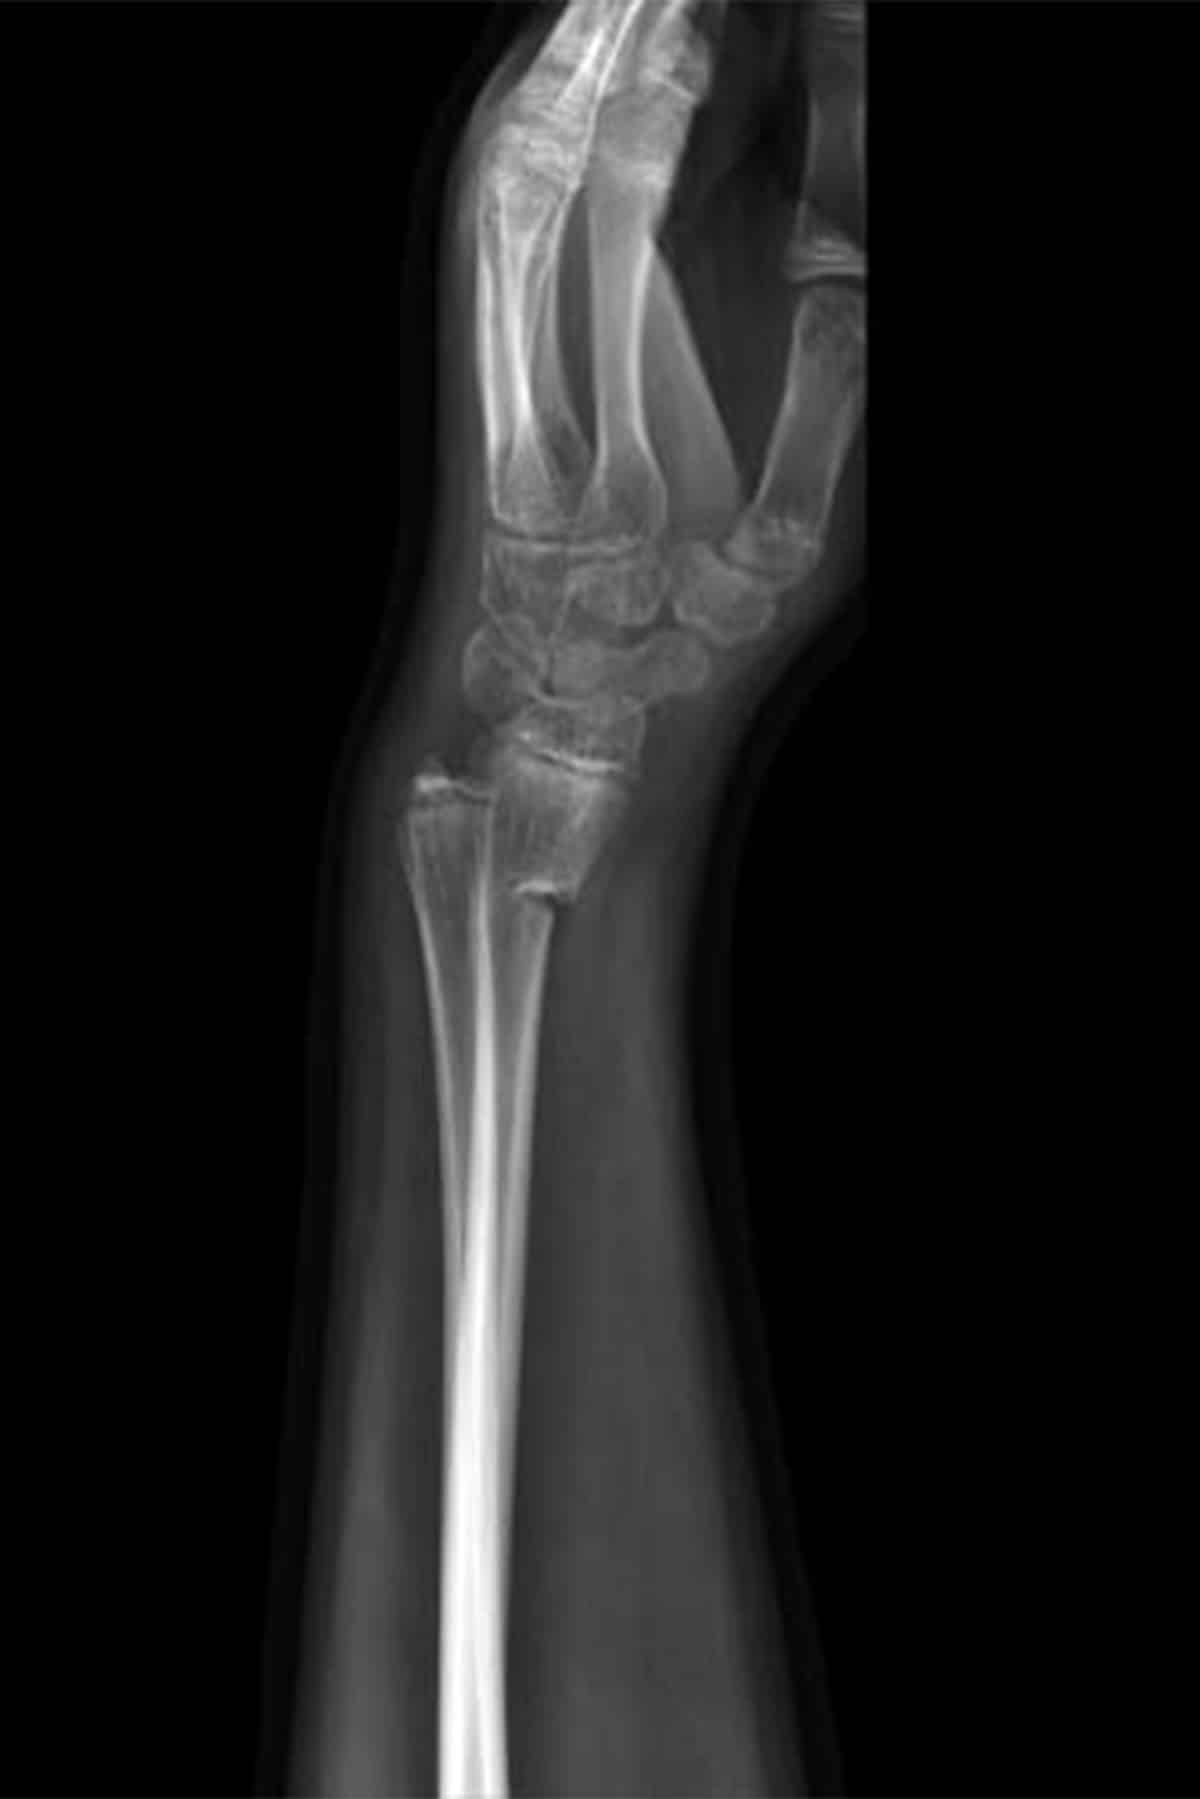

Parents of babies and children who have suffered from baby formula side effects may be entitled to compensation through filing a baby formula lawsuit against Nutricia or another manufacturer. Deficient in absorbable phosphorus, Neocate baby formula has been found to result in skeletal deformities, spontaneous fractures, and rickets. Through no fault of their own, parents and caregivers have fed their children Neocate formula and put them at grave risk. Families whose child suffered from health problems and injuries traced to unsafe baby formula may be eligible for compensation for medical expenses, pain, and damage by filing baby formula lawsuits.

2015: Nutricia receives first reports of broken bones and rickets from Neocate formula and repeatedly denies any link to its products.

2017: Yale / Mayo Clinic study confirms Neocate link to broken bones and rickets.